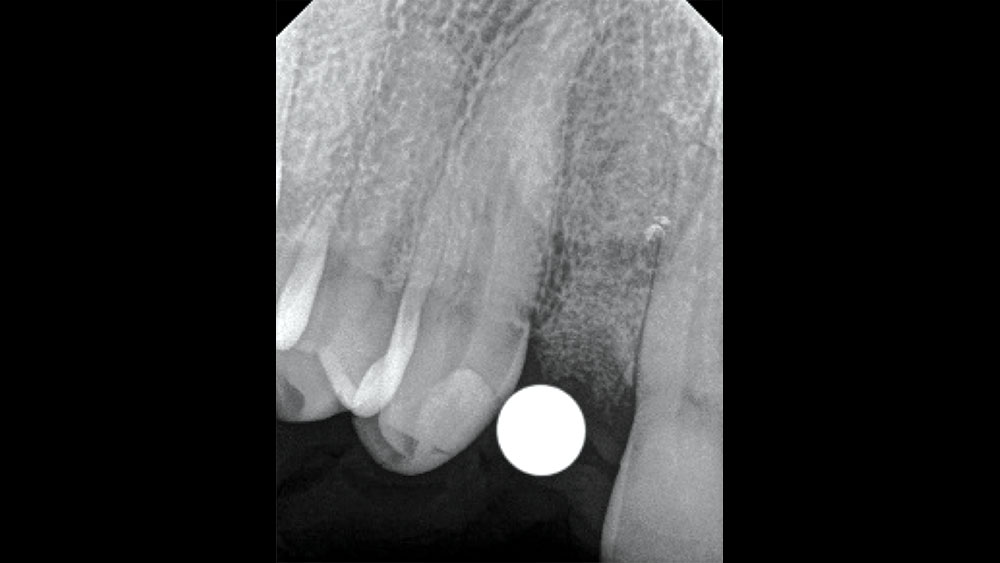

To achieve an optimal functional and esthetic outcome, the implant must be placed correctly with regard to trajectory, adjacent vital anatomy, and buccolingual, apicocoronal and mesial-distal positioning. Situating the implant so that the edges of the osteotomy are at least 2 mm from the buccal and lingual cortical plates, 2 mm from adjacent roots, 2 mm from vital structures, and 2–3 mm below the crest of tissue will keep the implant within the envelope of acceptability. The implant trajectory should emerge lingual to the incisal edge of the planned restoration, which allows for a screw-retained crown.

This case is an example of an ideal clinical situation for dentists who are new to placing implants in the esthetic zone. The patient requested treatment for a fractured upper lateral incisor. After extraction, grafting and healing, ample bone and soft tissue were present, and an implant was placed in optimal position for an esthetic result. The screw-retained restoration predictably restored form and function, illustrating the beautiful results that can be achieved by observing simple surgical and prosthetic guidelines.